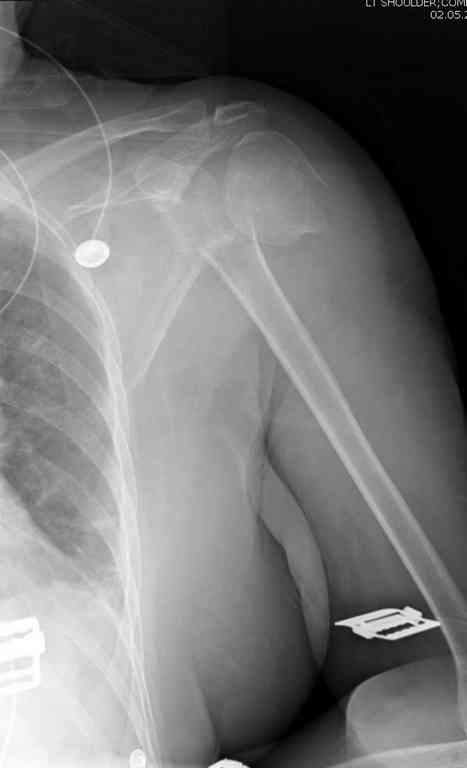

По Neer операцию рекомендовали только тогда, когда угол между диафизом и головкой составляет около 45 градусов, и переломы с меньшим углом смещения считали благоприятным для функционального результата.

Хотя "варусная импакция" в проксимальном отделе плеча срастается хорошо консервативными мерами, но в результате при восстановлении такие больные теряют часть отведения, и тем более у больной варус осложнен еще сгибанием.

Закрытые репозиции без фиксации из-за вторичного смещения неэффективны, поэтому рекомендуется репозиция с фиксацией. Методик много, кто чем владеет и отдает предпочтение закрытые-открытые, перкутанные, с блокирующими пластинами, гвоздь, множественными спицами или методом спиц по Лазареву, и осторожно с манипуляциями из=за возможности повреждения аксиллярного нерва - частый вид осложнении.

Первичное консервативное лечение рекомендуется только тем больным, когда по причинам общего состояния, например, политравма или другие тяжелые состояния больного, не позволяют оперативное лечение при первичном поступлении, тогда такие больные с самого начала предупреждаются о необходимости вальгусной или другой восстановительной операции позднее.

Неправильно выбранная тактика по фиксации или технические ошибки во время операции могут привести к серьезным осложнениям. Здесь привожу

пример из нашей практики, вроде обычный перелом шейки, фиксированный популярным методом "Сиэтла" - множественными спицами 2.8 мм с резьбой на конце.

При первичном осмотре в поликлинике через 3 недели обнаружили миграцию двух спиц, срочно госпитализированному на второй день перед операцией на всякий случай сделали снимок, одна спица находилась под ключицей в шейном отделе (на снимке).